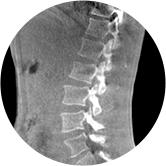

颈椎

腰椎